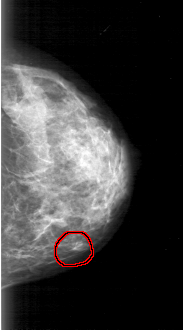

D_4031_1.LEFT_MLO

LEFT_MLO LINES 5221 PIXELS_PER_LINE 3136 BITS_PER_PIXEL 12 RESOLUTION 43.5 NON_OVERLAY